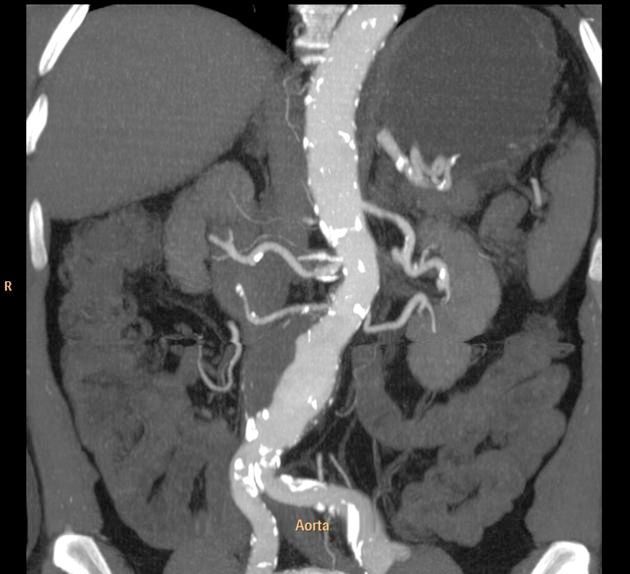

Giant cell arteritis (GCA) is the most common form of adult vasculitis in the United States and can be subdivided into those with cranial only symptoms, those with large vessel vasculiti/PMR, and those with mixed features. Non-invasive imaging is key in detecting large vessel